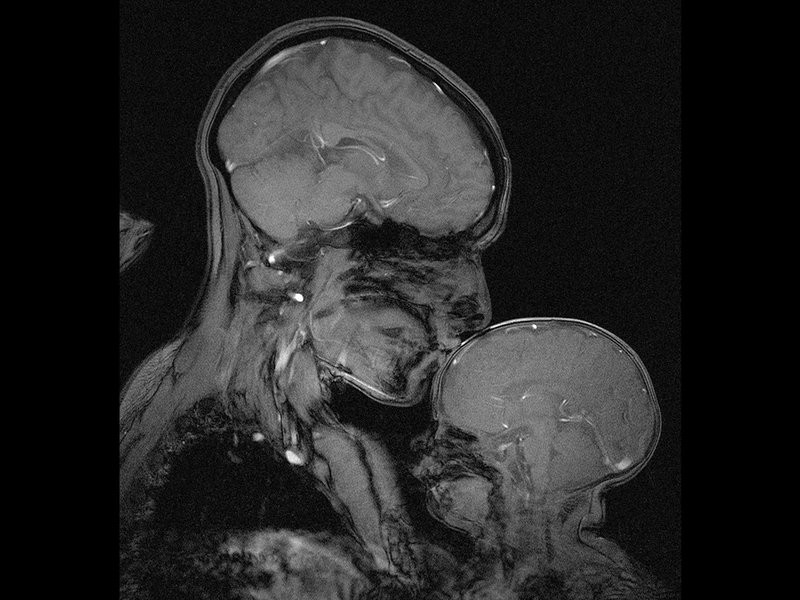

Gledate u prvi snimak majke i deteta ikada napravljen magnetnom rezonancom. Napravila ga je neuronaučnica Rebeka Sejks, a snimak prikazuje upravo nju i njenog dvomesečnog sina Persija.

Sejks radi na Odeljenju za mozak i kognitivne nauke pri Em-Aj-Tiju, kao profesorka kogitivne neuronauke Bavi se proučavanjem teorije uma, tj. načina na koji ljudi misle o mislima drugih.